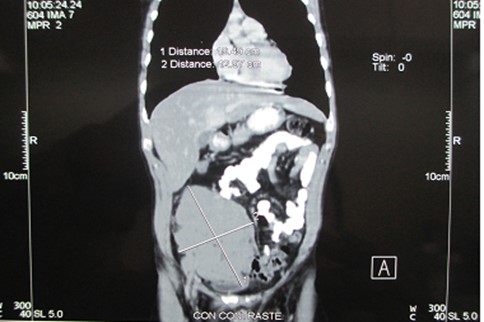

Con el diagnóstico histopatológico, se realizó en el post operatorio estudios de extensión, la Tomografía torácica - abdominal (Figura 6), mostró una masa solida isodensa de 20 x 13 cm, de bordes regulares que desplaza estructuras adyacentes y no invade otros órganos, además no se evidenció masas ni adenopatías en tórax, mediastino y resto de abdomen. El paciente recibió protocolo CODOX-M / IVAC con mejoría clínica, se realizó 6 meses después una TAC abdominal, donde ya no se evidenció la tumoración inicial, el paciente evolucionó favorablemente. A los 6 meses el paciente se encuentra estable y controlado

Figura 6 Masa solida isodensa de bordes regulares que desplaza estructuras adyacentes, pero no las invade

El linfoma de Burkitt es un linfoma de células B raro y agresivo que generalmente involucra sitios extranodales. Existen tres variantes clínicas que son la endémica, la esporádica y la asociada a la inmunodeficiencia10,11. La variante endémica es la forma más común en niños, que es más frecuente en África Ecuatorial. La forma esporádica representa 1-2 % de todos los linfomas y puede estar asociado a la infección por el virus Epstein-Barr (EBV)10. Una vez establecido el diagnóstico se debe evaluar actividad en otras áreas10, como ganglios periféricos e infiltración a médula ósea, En nuestro caso se realizó tomografía torácica-abdominal (Figura 6) que muestra una lesión tumoral en solida de 20x13 cm en hemiabdomen inferior de bordes regulares, que desplaza las estructuras adyacentes, no se evidenció lesiones ni adenopatías en tórax, mediastino y resto de abdomen.